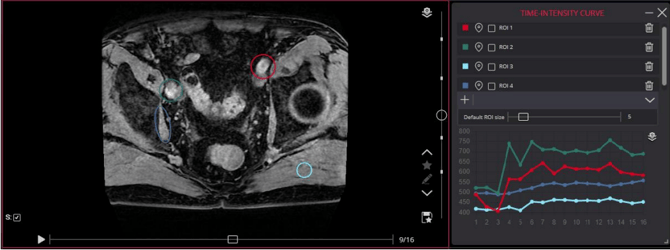

- You can now select and draw multiple regions of interest (ROIs) on the images. The TIC tool will graph the intensity changes over time within these ROIs, allowing for a detailed assessment of tissue response to contrast over time.

- Real-time feedback, with the curve, is automatically updated as you adjust the ROIs or move through the different phases.